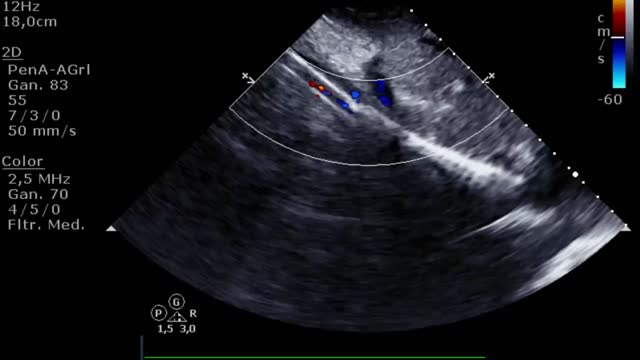

El aumento de la poscarga que condiciona la ECMO, junto con la baja contractilidad ventricular izquierda, puede comprometer la apertura valvular aórtica, pudiendo presentar un cierre precoz de la válvula (suplementario 13) e incluso permanecer cerrada (fig. 3 y suplementario 14).

El cierre aórtico es una complicación indeseada y que se debe resolver ya que, si se perpetúa, condiciona una estasis sanguínea a nivel intraventricular y un aumento de las presiones izquierdas que se traduce en una dilatación de cavidades izquierdas y, finalmente, en edema pulmonar persistente. En caso de que esto ocurra, en la ETT podremos ver humo o incluso trombos intraventriculares y signos de altas presiones (una relación E/A>2 y/o un tiempo de desaceleración del flujo mitral<150ms) izquierdas. Además de la utilidad diagnóstica/evolutiva, la ETT nos ayudará a guiar el tratamiento de esta complicación mediante la evaluación de la rentabilidad del uso/aumento del tratamiento inotrópico (suplementario 21) o guiando la implantación de dispositivos (BCIAo/Impella®) o intervencionismos (septostomía auricular, drenaje apical, ECMO veno-arterial de aurícula izquierda) para la descarga de presiones izquierdas12.